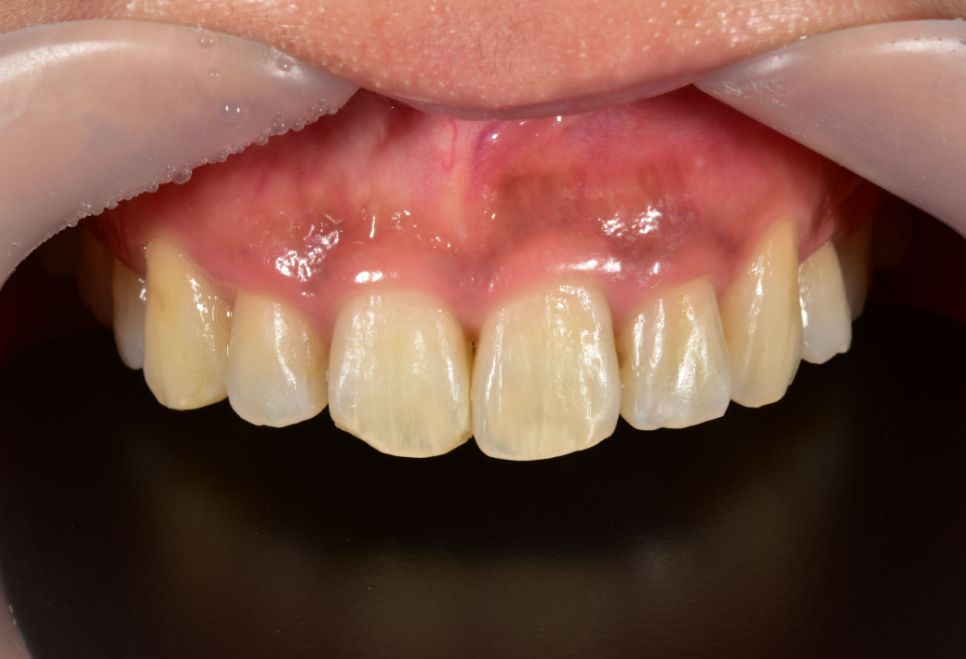

무삭제 라미네이트

블랙필름

오늘은 이러한 앞니깨짐을 치료하기 위한 치아무삭제로 진행되는 앞니라미네이트에 대해서 자세히 알아보도록 하겠습니다.

투디치과 무삭제 라미네이트 전용 [블랙필름]은 우수한 심미성을 가지고 있고 레진보다 강도나 마모 저항성이 우수하는 장점을 가지고 있어 앞니가 약간 깨진 경우 앞니깨짐을 치료할 뿐만 아니라 심미성까지 함께 개선이 가능합니다.

무삭제라미네이트 블랙필름의 특성상 얇기가 매우 얇아야하며 투명함으로 인해 치아의 모든 표면이 비쳐보여 보정과 색상재현 등 환자분에게 맞는 맞춤 제작이 100% 수제작으로 진행되는 필름입니다. 그리고 가장 큰 장점인 치아를 전혀 삭제하지 않고 필름을 제작한다는 점입니다.

이외에도 환자분마다 가지고 있는 교합의 특성, 식사 시 턱의 움직임, 이갈이와 같은 습관들, 치열의 삐뚤거림, 방송촬영 여부 등 다양한 요소를 고려하여 맞춤 제작 되기 때문에 수명 또한 길어지는 장점이 있습니다. 그리고 모든 위의 요소들을 고려하여 필름이 맞춤 되작되기 때문에 내원해주시는 환자분의 치료 만족도가 상당히 높은편입니다.